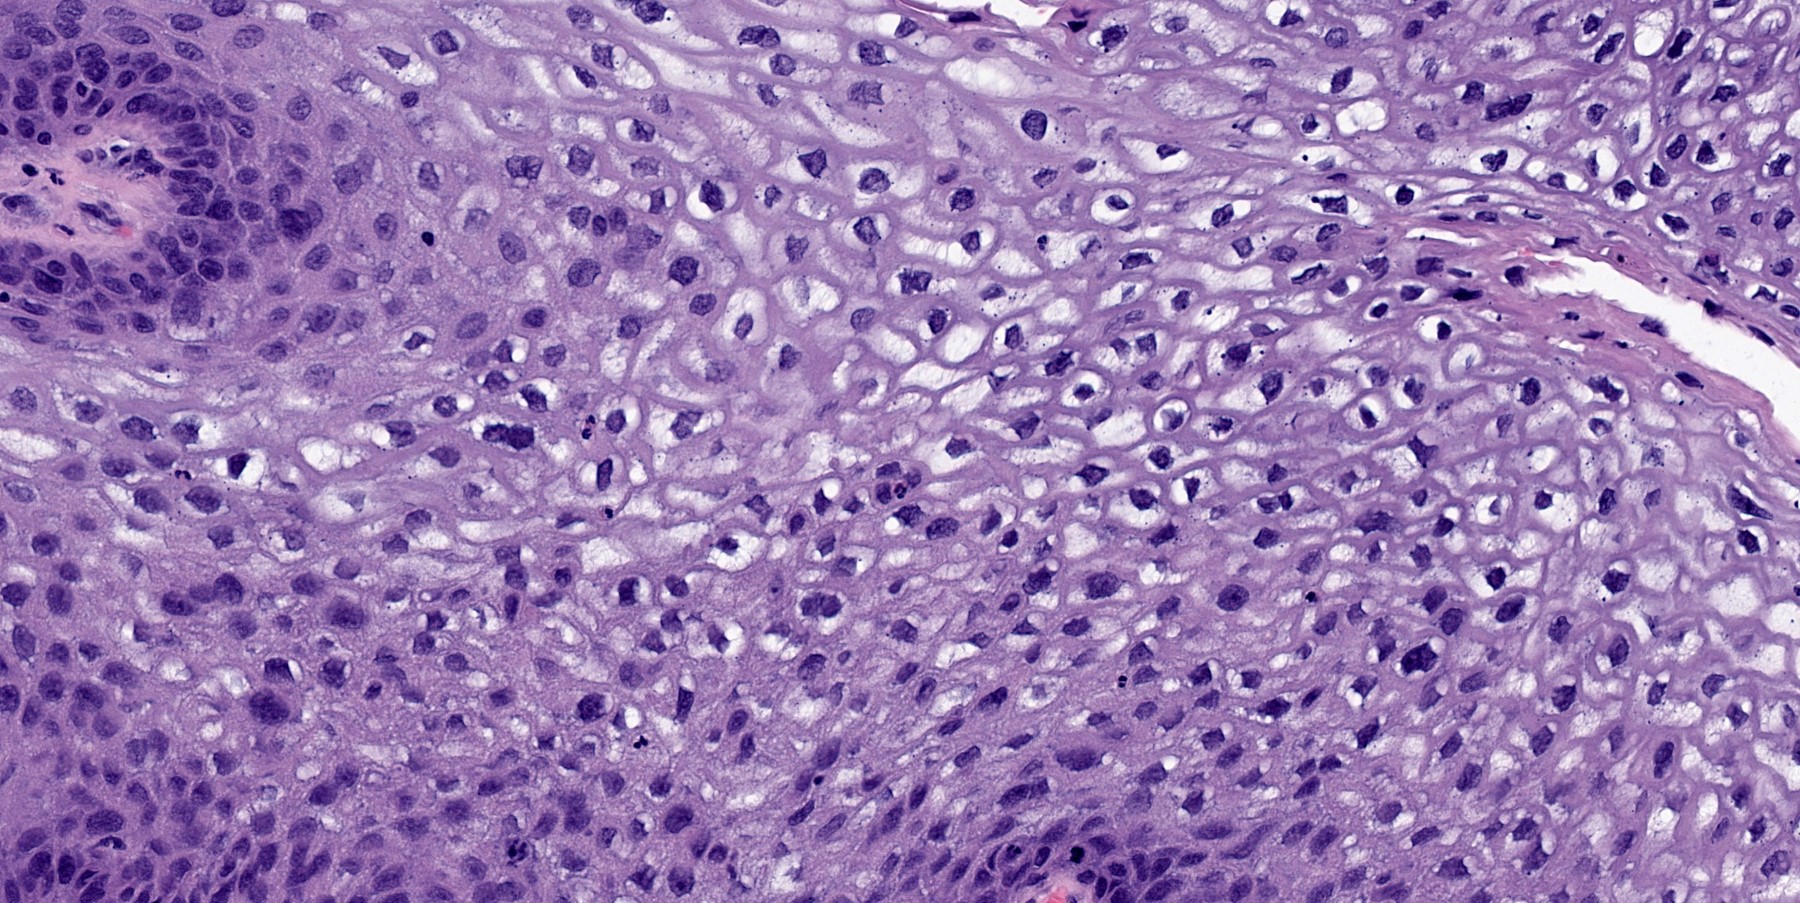

Microscopic (histologic) description

- Finger-like projections or multiple fronds with a central fibrovascular core, covered by benign hyperplastic stratified squamous epithelium

- Basal and parabasal hyperplasia

- Increased mitotic figures in the basal and parabasal layers

- Koilocytic changes in upper layer: may be pronounced or subtle

- Surface keratinization: absent to minimal

- Malignant transformation is characterized by aberrant (paradoxical) keratinization, marked cytological atypia, focal necrosis, increased mitoses and atypical mitoses not limited to the basal and parabasal layers, as well as invasive growth pattern (Respir Med 2017;126:116)

Microscopic (histologic) images

B. Squamous papilloma. The H&E image shows a squamous papilloma, a benign squamous proliferation with papillary projections.